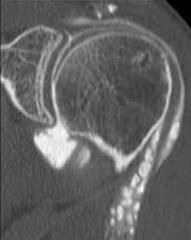

OSTEOCONDROMATOZA GLENO-HUMERALA

Ansamblul receselor articulare si spatiul bicipital sunt ocupate de osteocondroame confirmate IRM